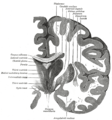

المهاد Thalamus (من اليونانية θάλαμος = المهد أو المخدع, غرفة) هو زوج وجزء متماثل في المخ. وتشكل الجزء الرئيسي من diencephalon.

المكان والتضاريس

التشريح